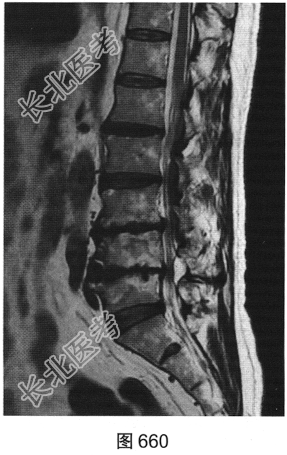

- 多项选择题3.[提示]患者行腰椎MRI检查,如图660~图663所示。患者MRI的T2压脂像上, 部分椎体上、下缘高信号提示( )

A、椎体感染所致的骨髓水肿

B、肿瘤侵蚀破坏

C、椎体轻度压缩骨折

D、脊椎结核

E、退变所致的终板炎

F、椎体脂肪化

- 多项选择题4.综合X线、CT和MRI图像,该患者有以下哪些腰椎退变征象( )

A、终板炎

B、腰椎间盘突出

C、许莫结节

D、黄韧带肥厚

E、腰椎管狭窄

F、腰椎间盘脱出,髓核游离